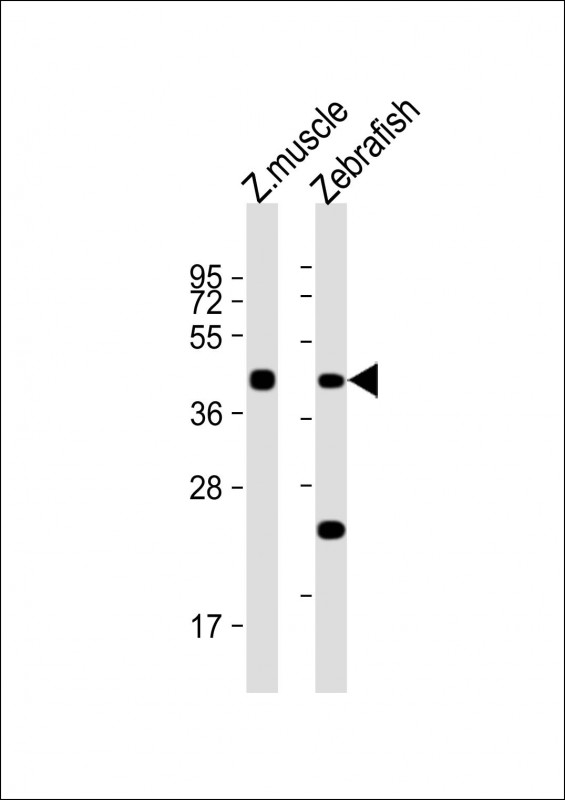

- Immunohistochemical analysis of paraffin-embedded human bladder cancer tissues using BRAF mouse mAb with DAB staining.